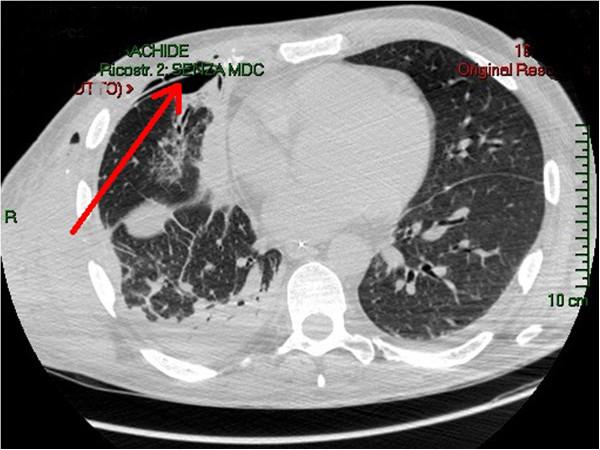

Despite progress in reconstructive techniques, rebuilding portions of the thorax remains challenging, in particular when large resections, contamination or infection are involved. No other cases of thoracic reconstruction in trauma patients with biological prosthesis have been described since now.

We report a case of thoracic reconstruction in highly infected field in a trauma patient. We also performed a literature review about the topic.

Collamend® demonstrated its usefulness in thoracic wall reconstruction even in trauma patients and infected fields.

尽管在重建技术方面取得了进展,但重建胸部部分仍然具有挑战性,特别是在涉及大切除、污染或感染的情况下。自那时以来,尚未有其他关于创伤患者使用生物假体进行胸部重建的病例报道。

我们报告了 1 例创伤患者在高度感染的情况下进行的胸部重建。我们还对该主题进行了文献回顾。

Collamend®在胸壁重建中表现出了其有效性,即使是在创伤患者和感染部位。